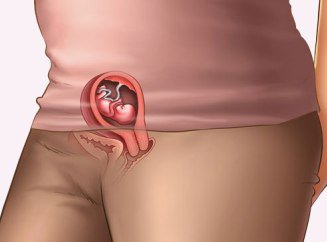

Місячні в перші 4-5 тижнів вагітності цілком допустиме явище. Відбувається це тому, що запліднення відбулося в середині циклу, але запліднена яйцеклітина могла не дійти до порожнини матки, так як на це йде 7-15 днів.

Відповідно гормональний фон ще не встиг змінитися, тому організм відреагував як завжди – звичайні місячні почалися і закінчилися. Дане явище повторитися в наступному місяці не повинно. Буває так, що естрогенний фон нижче, ніж потрібно, але гормони вагітності вже працюють, а рівень естрогенів раптом впав по всіляких фізіологічних причин. Таке явище завжди викликає кров'янисті виділення, і що характерно, вони наступають саме тоді, коли за планом повинні були початися місячні, не будь вагітності.Оскільки в наш час стабільний гормональний фон є досить рідкісним явищем, деякі жінки без загрози переривання вагітності можуть менструювати 3-4 місяці. Крім того, у медичній практиці зустрічаються випадки дозрівання двох яйцеклітин одночасно (з різних яєчників, зазвичай це відбувається по черзі), а коли запліднюється одна з них, то друга відторгається і викликає менструацію, але ситуація така досить складна й рідкісна.

Що стосується місячних під час вагітності - вони можуть, у рідкісних випадках. Відбувається це тому, що кожен місяць яйцеклітини виходять по черзі з різних яєчників, т. е. лівий-правий, лівий-правий. І якщо організм не встиг перебудуватися, другий яєчник може випустити яйцеклітину, що веде до місячних.